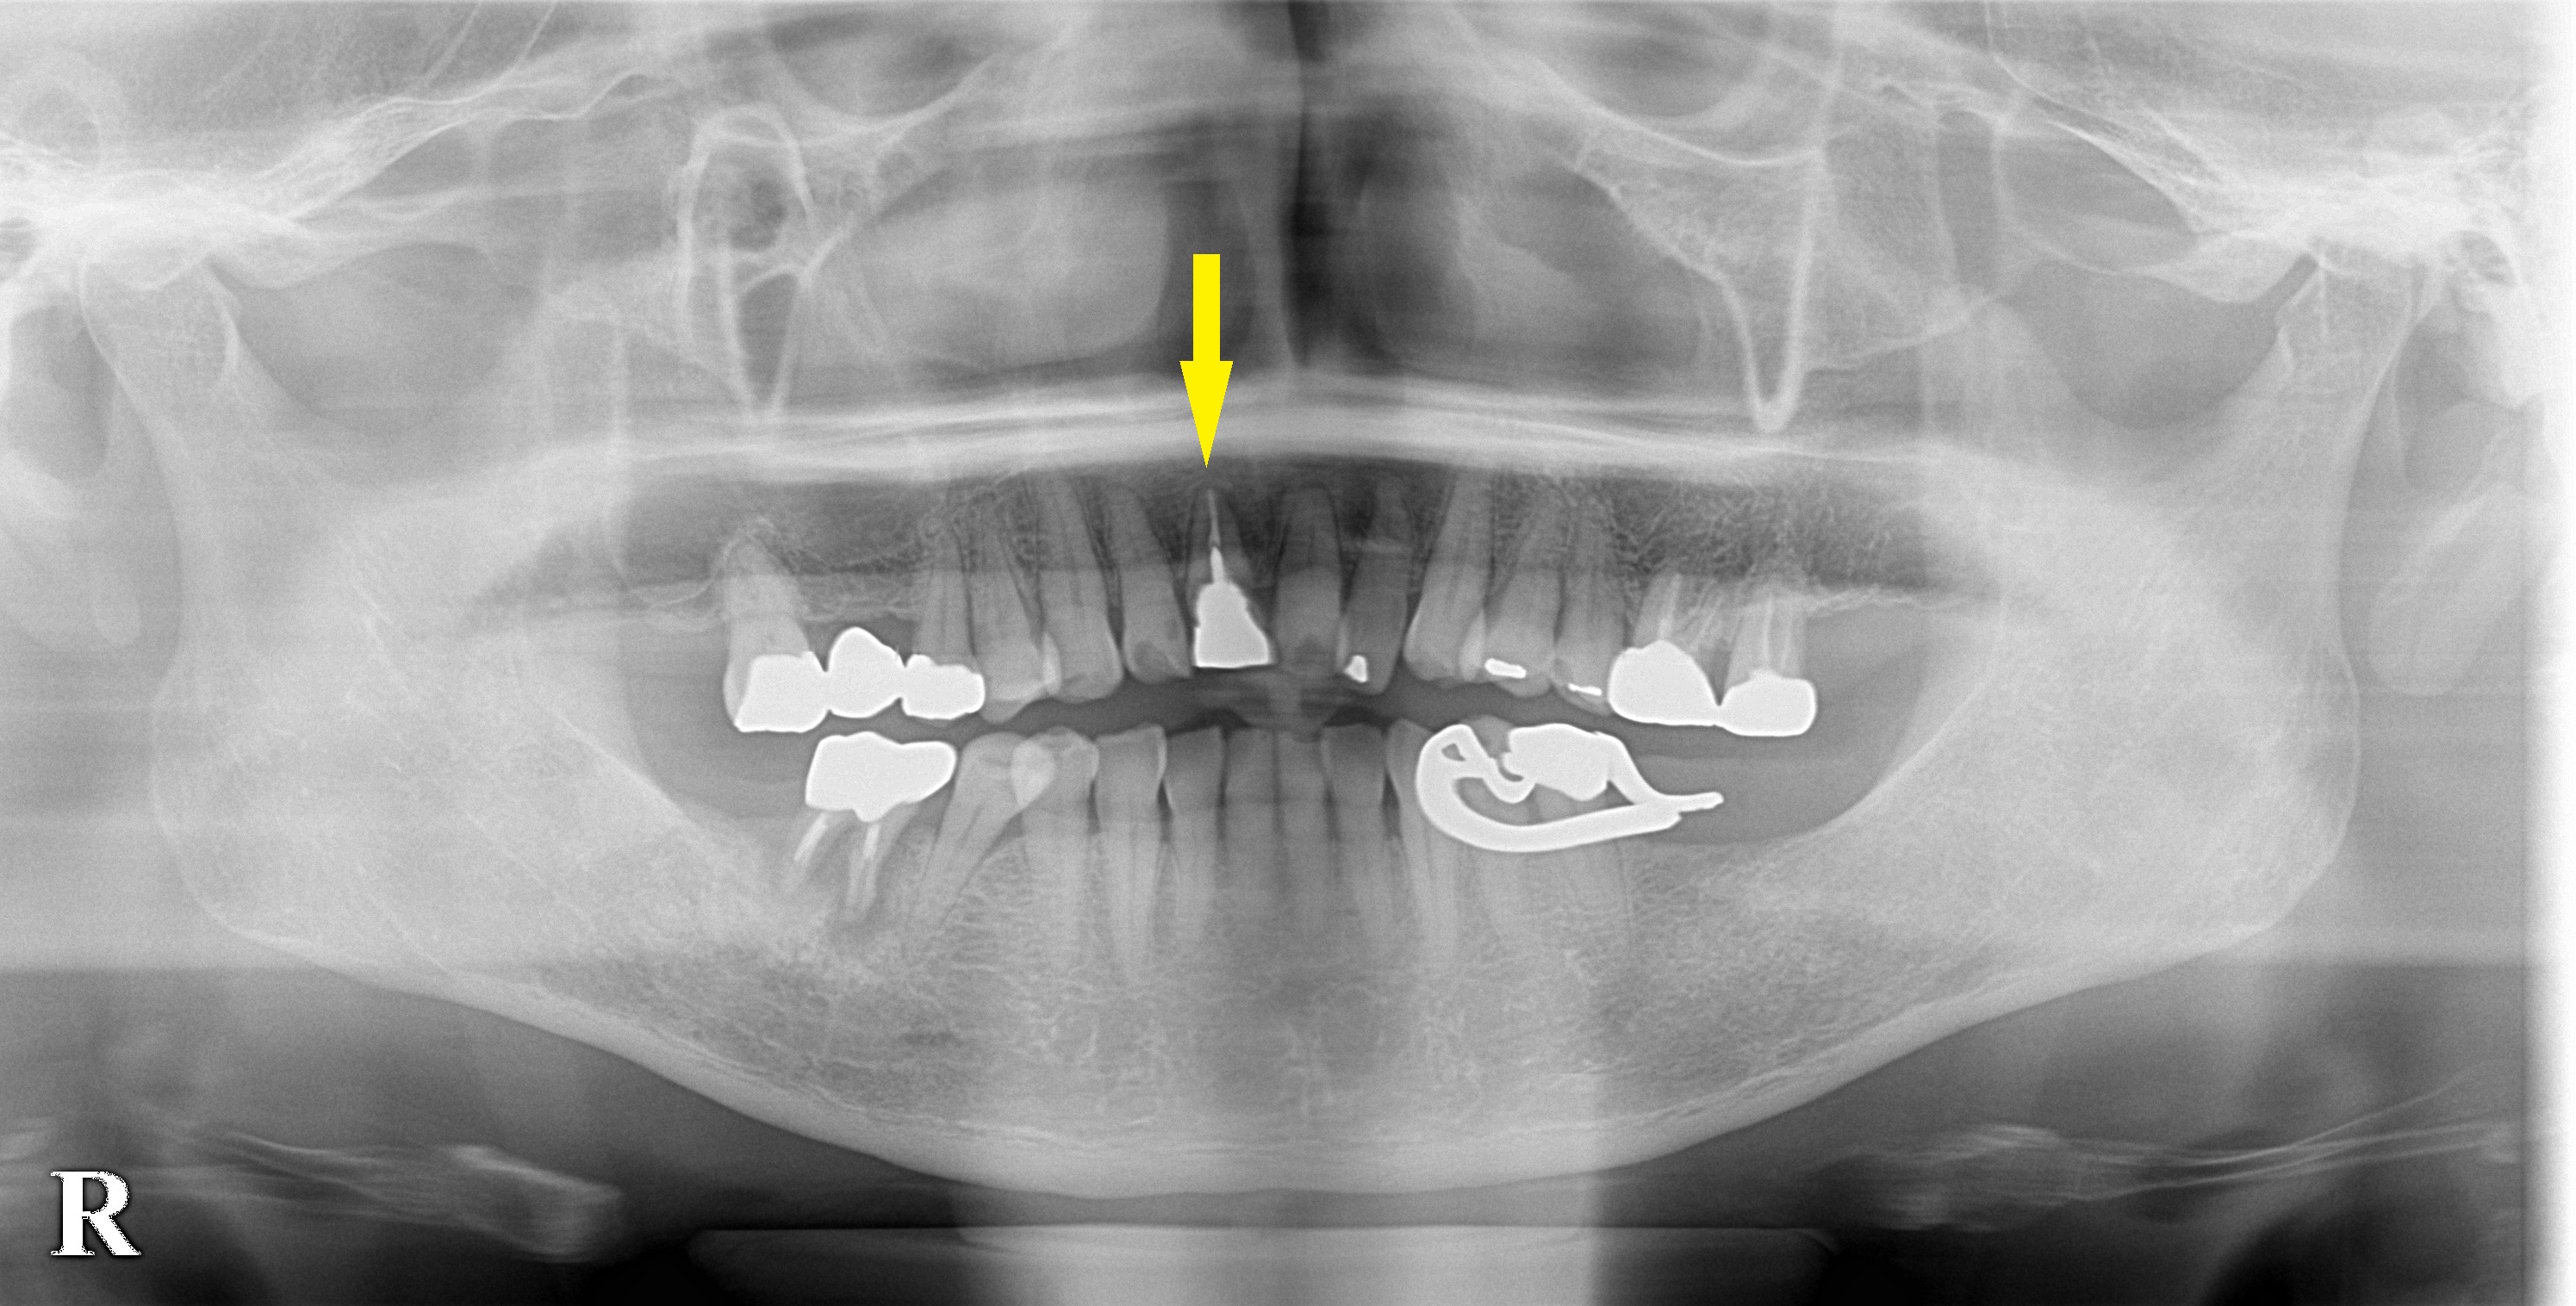

CTを撮ってみると、2段目左側の写真の黄色矢印部分で破折しているようでした。

本日、埋入手術を行ない、手術後のCTにて、インプラント体がしっかり埋入され、インプラントの外側に骨補填材がいい感じで、填入されていることが、確認されています(2段目右側の写真の矢印部分)。